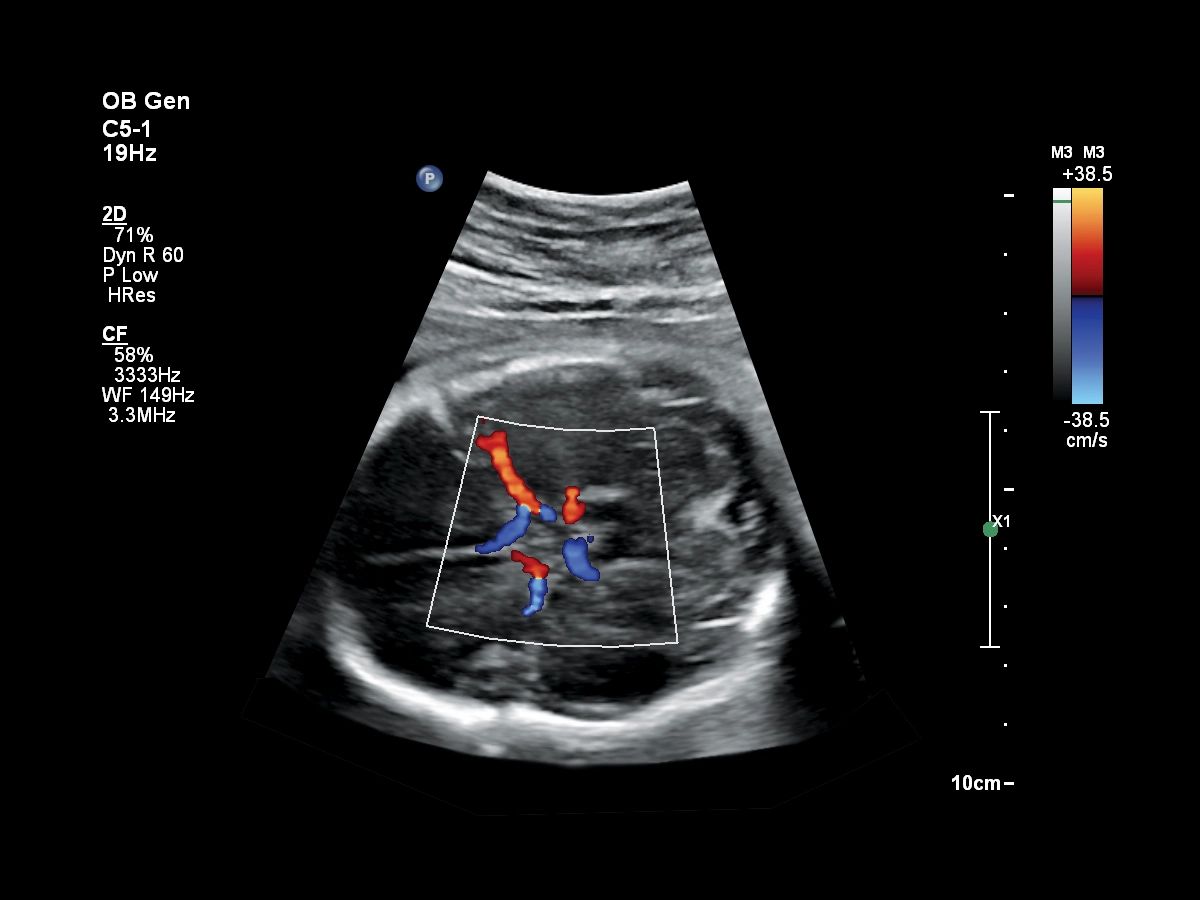

Функции для гинекологии и акушерства

- Free Hand 3D - возможность реконструкции 3D изображения при помощи линейного или конвексного датчика

- 4D Imaging - автоматическая визуализация 3D/4D изображения

- TrueVue - виртуальный источник света для получения качественного 3D/4D изображения

- FlexVue - опция для визуализации 3D изображений в плоскости

- aBiometry Assist - автоматические биометрические измерения

- Режимы 3D\4D для визуализации и анализа объемных данных